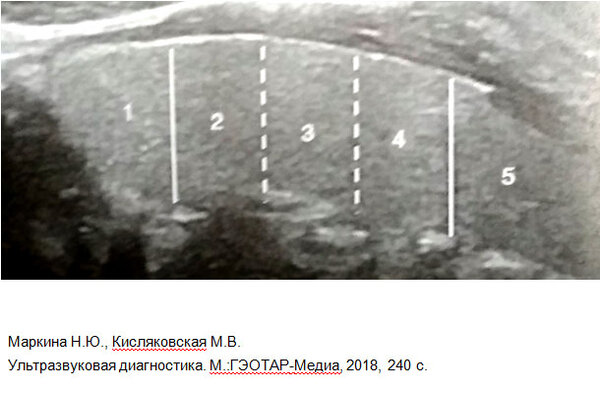

На схеме показаны: 1 — капилляры вокруг фолликула, 2 — клетки фолликула (тиреоциты), 3 — артериола, 4 — ядра тиреоцитов, 5 — коллоид с гормонами внутри фолликула.